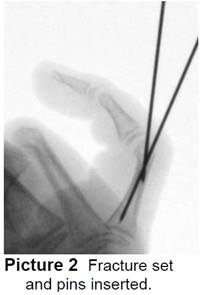

- The surgeon will do a closed reduction and/or pinning. Pins are pushed into the skin to hold the pieces of bone together until the they heal (Picture 2). The ends of the pins on the outside of the skin are bent (Picture 3).

- At the end of surgery, your child’s hand will be in a cast or splint and the pins are covered up.